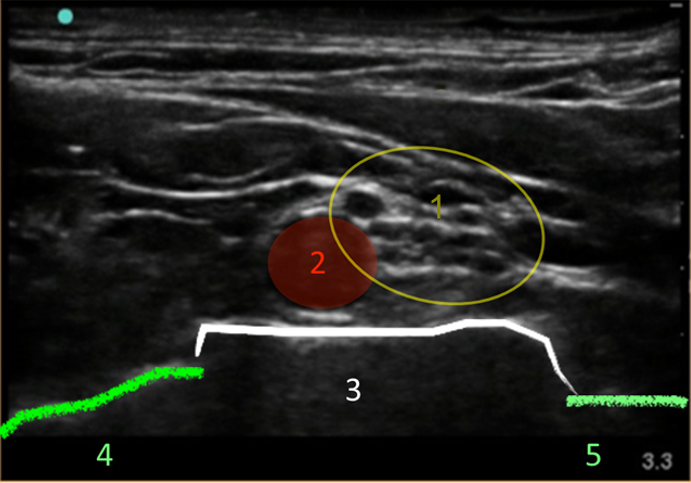

Supraclavicular Brachial Plexus Nerve Image

Brachial Plexus

Artery

1st Rib

Pleura